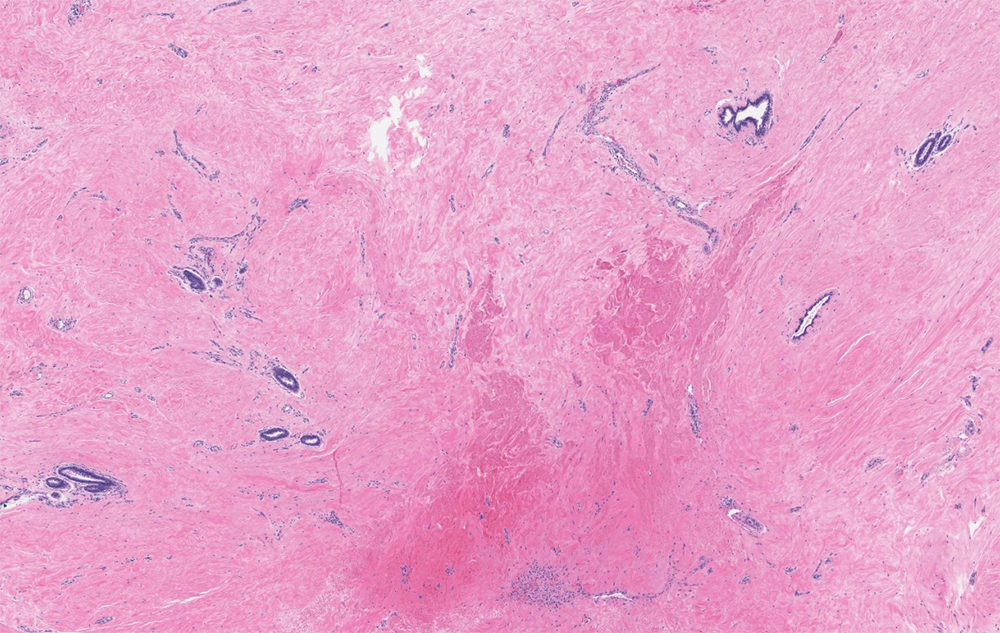

Radial scar

Stellate, dense fibroelastosis with entrapped glandular structure in a radiating configuration. Two cell layers are maintained throughout the lesion. May have associated epithelial lesions (UDH, ADH, DCIS).

Radiographically presents as a spiculated lesion, which may have associated calcifications. Approximately 2/3 have a PIK3CA mutation.

Myoepithelial IHC helps exclude an invasive carcinoma.

Confers a 1.5-2 fold risk of invaive carcinoma, with a life-time risk of 5-7% in either breast (regardless of the laterality of the radial scar).